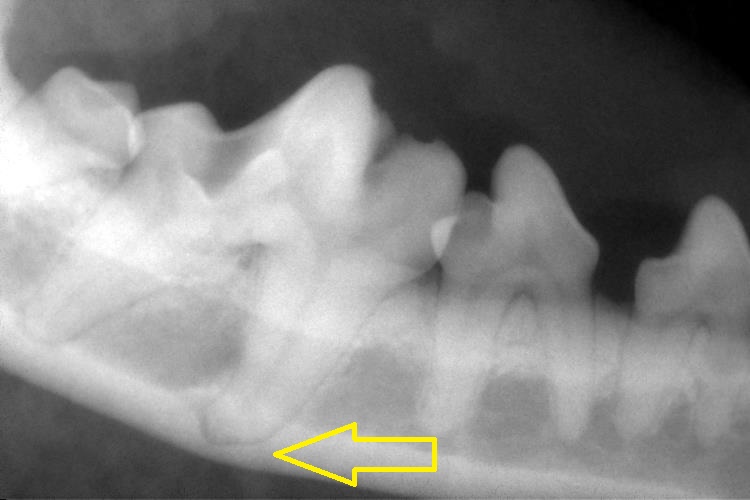

歯科レントゲン検査

歯槽骨の吸収はみられませんでしたが、右下顎の第1後臼歯部分の下顎骨はとても薄いことがわかりました。

また、この右下顎第1後臼歯も、術前に抜け落ちた歯と同様に変形歯でした。歯根部が湾曲しているため、将来、上顎と同じく根尖病巣が起こる確率が高くなります。この部分の下顎骨が薄いこともあり、歯周病が進行すると下顎が骨折してしまう可能性があります。